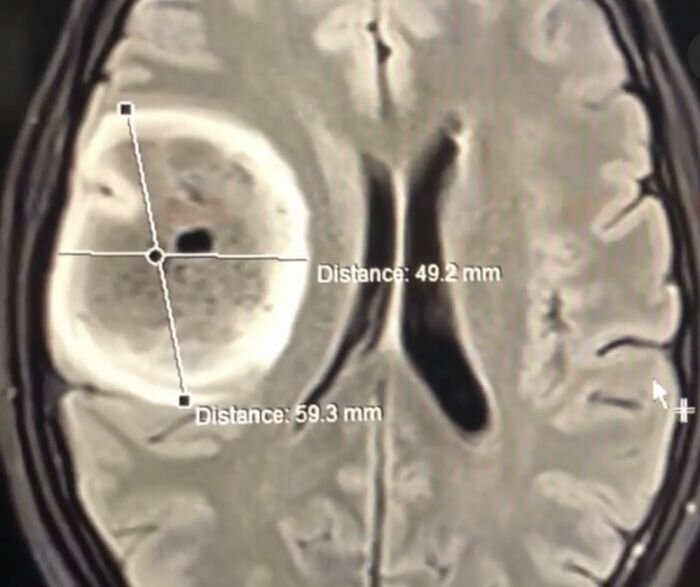

Astrocytoma is a brain tumor